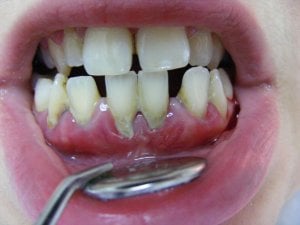

Ortodonti tedavisi adı verilen diş teli tedavisi hangi yaşta uygulanmalıdır? Tedavi süresi nekadar sürer? Süt ...